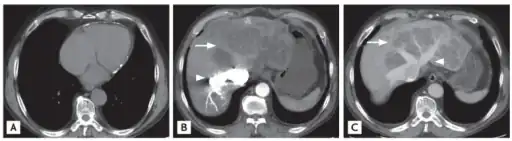

a) Sparse pericardial calcification with eccentric wall thickening b,c) liver CT shows variable regions of low attenuation, often called the “nutmeg liver” arrows -